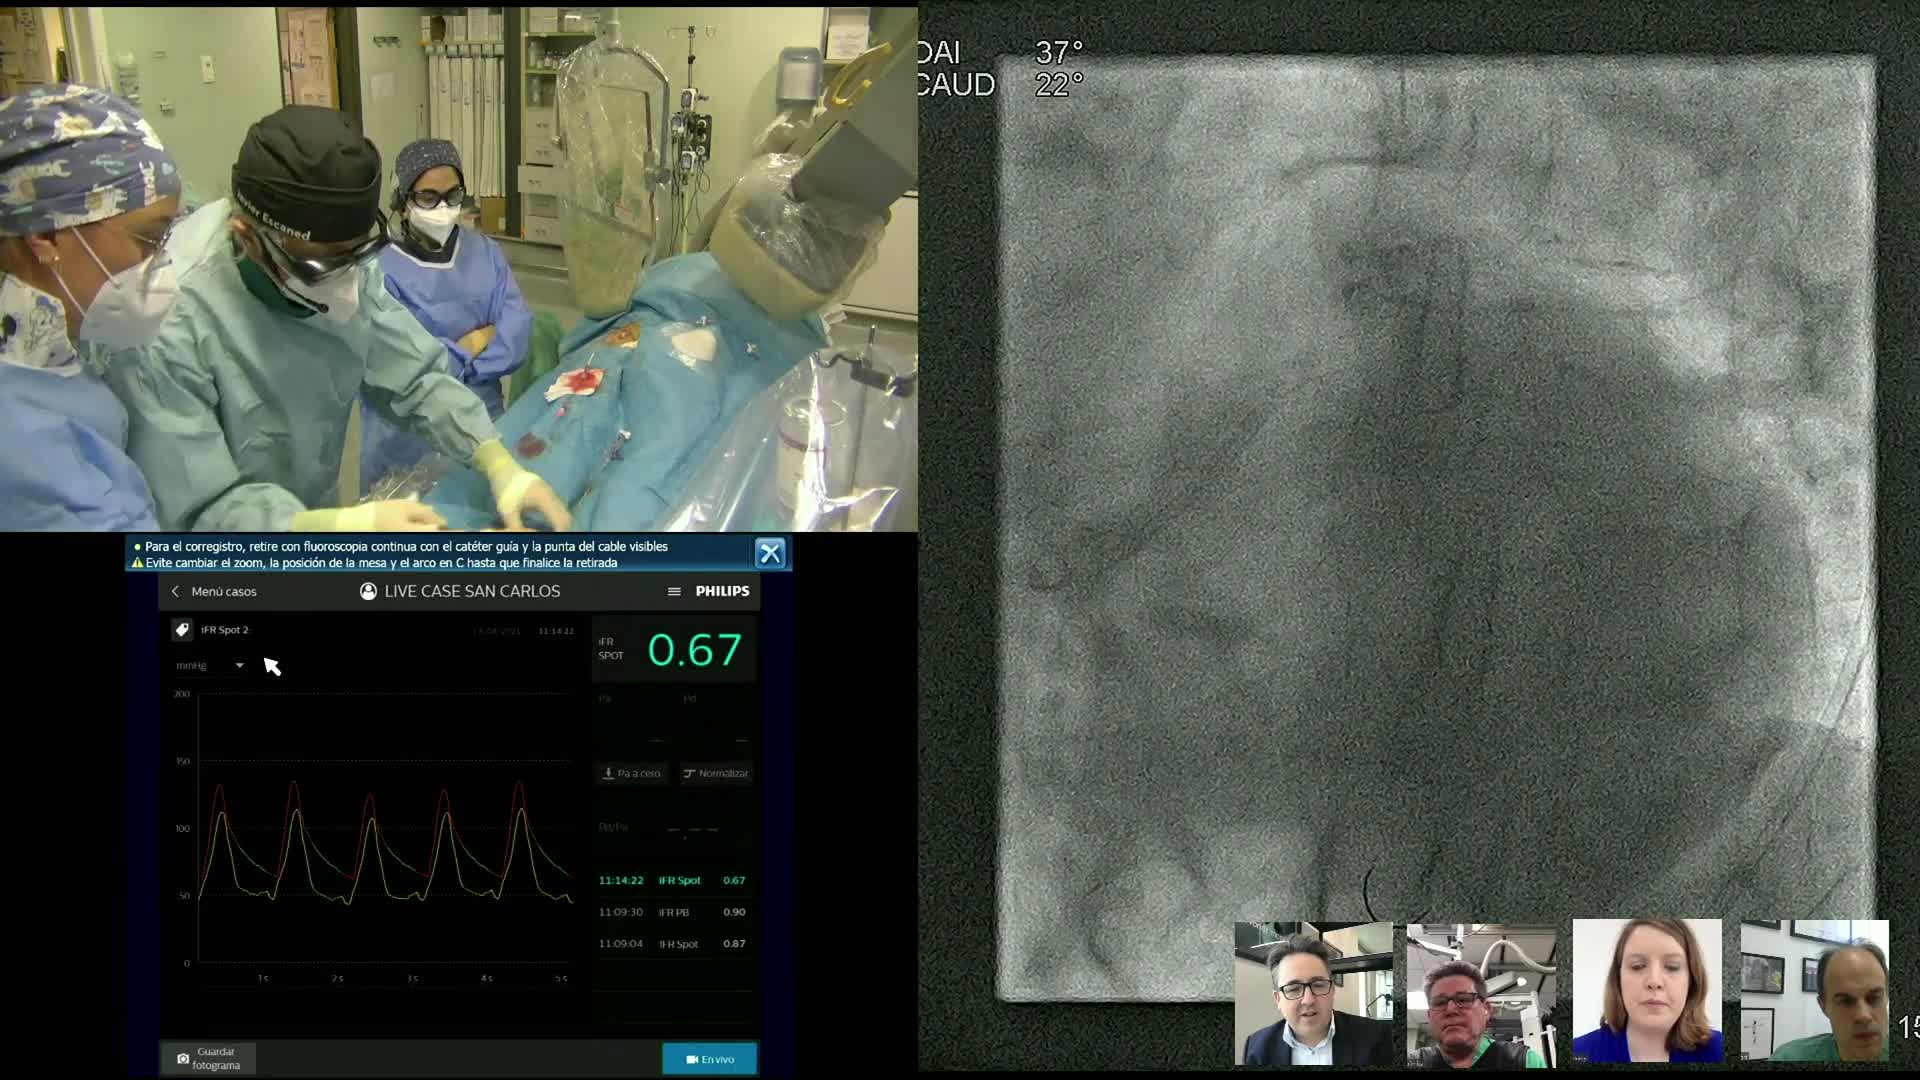

Complex PCI eCourse Madrid 26th October 2020

Complex PCI eCourse Madrid 27th October 2020

Complex PCI eCourse Madrid Day Two